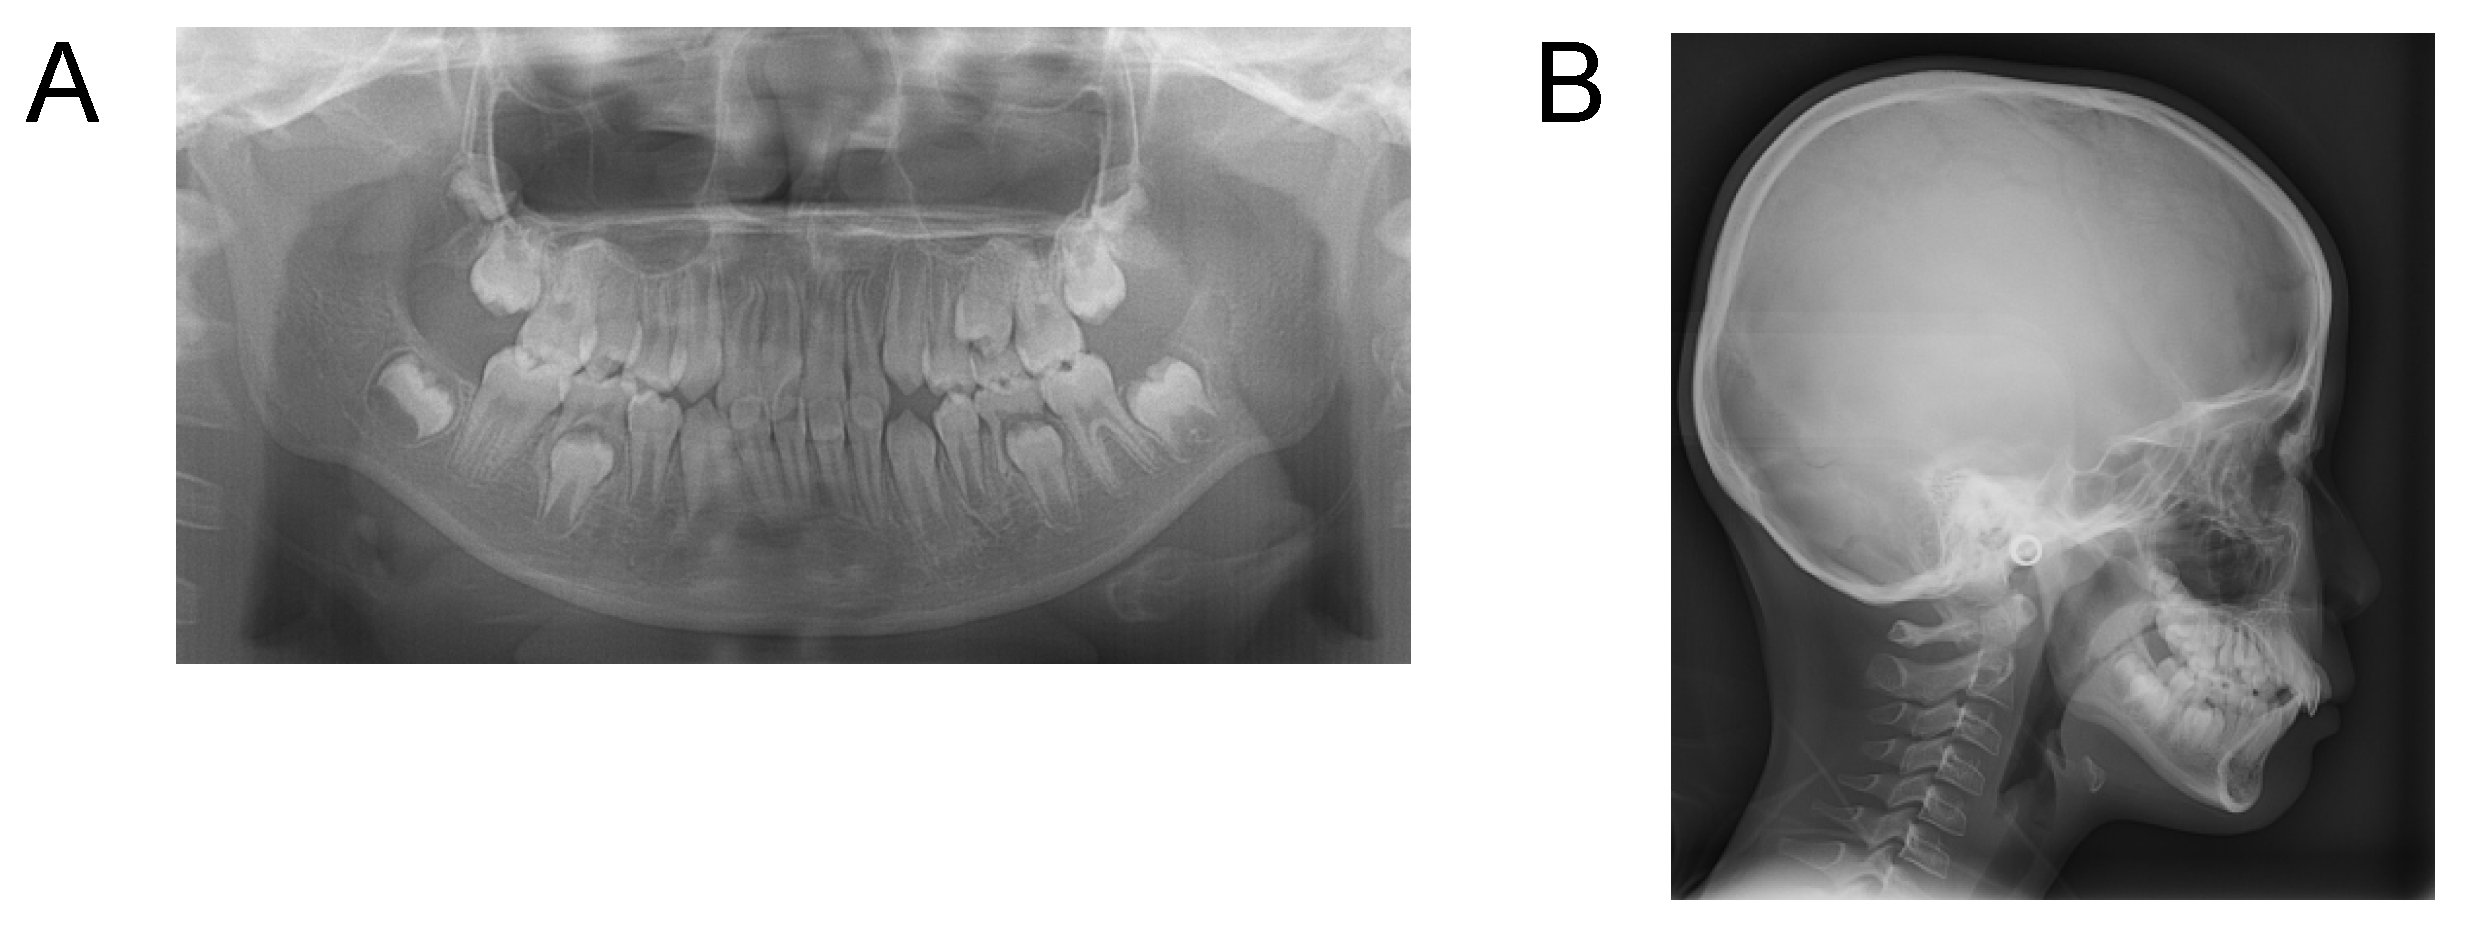

Case 3. Findings from initial examination